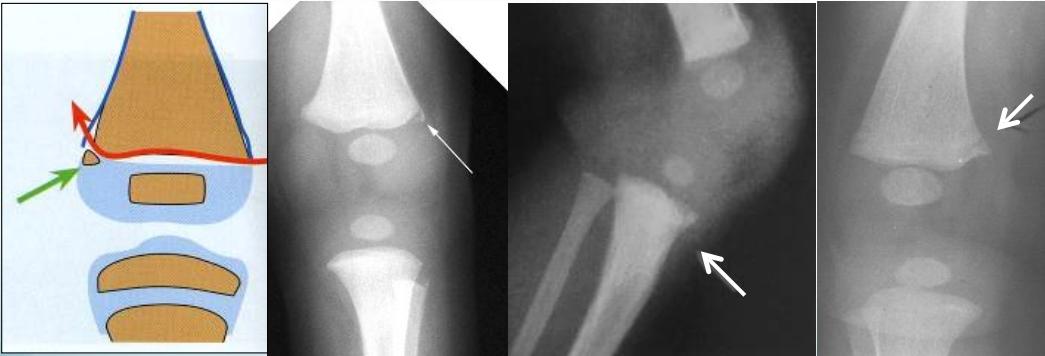

- Specific patterns:

- Corner fractures (traction & rotation)

- Bucket-handle fractures (traction & rotation)

Corner Fractures:

Bucket Handle Fractures: